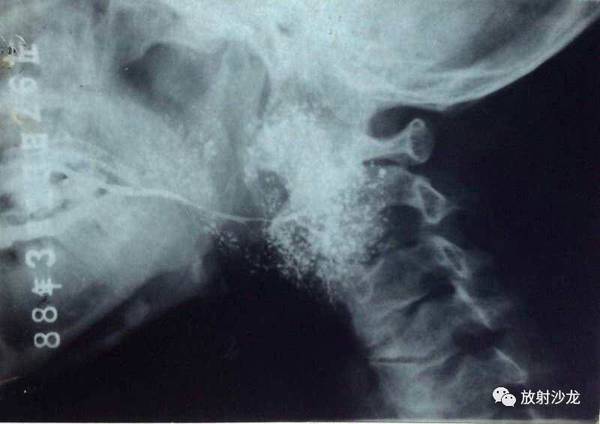

腮腺造影

左腮腺造影侧位,主导管自腮腺导管口斜向后下方,越过下颌升支,逐级